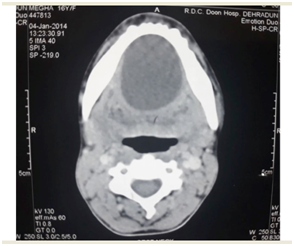

FNAC revealed epidermal inclusion cyst. Contrast enhanced CT imaging of the neck was done and it showed a mass measuring 8 × 8 cm with a clear boundary and regular margin positioned under the platysma anterior to the bilateral submandibular gland. Margin was enhanced in a ring pattern and the mass displaced the submandibular gland posteriorly (Figure 2).

Figure 2 Contrast enhanced CT imaging of the neck was done and it showed a mass measuring 8 × 8 cm with a clear boundary and regular margin positioned under the platysma anterior to the bilateral submandibular gland. Margin was enhanced in a ring pattern and mass displaced submandibular gland posteriorly.